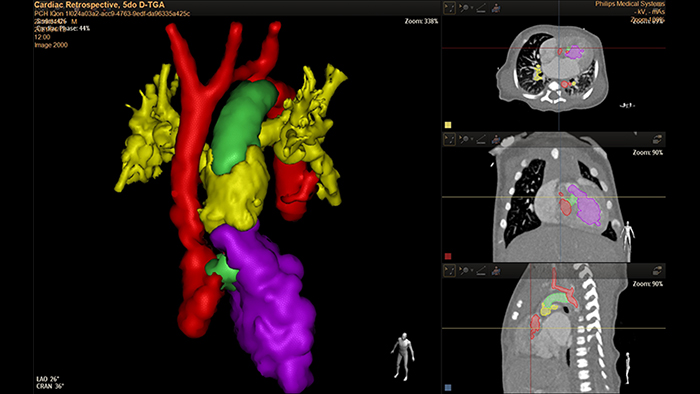

5-day old D-TGA analysis with HeartNavigator